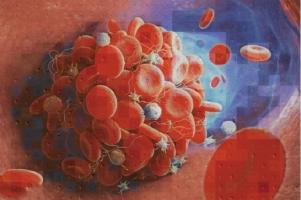

CAILLOT SANGUIN : Oui mais de quel type ?

Actualité publiée le 15/05/2020EXERCICE PHYSIQUE : Il stimule l’apprentissage et la plasticité